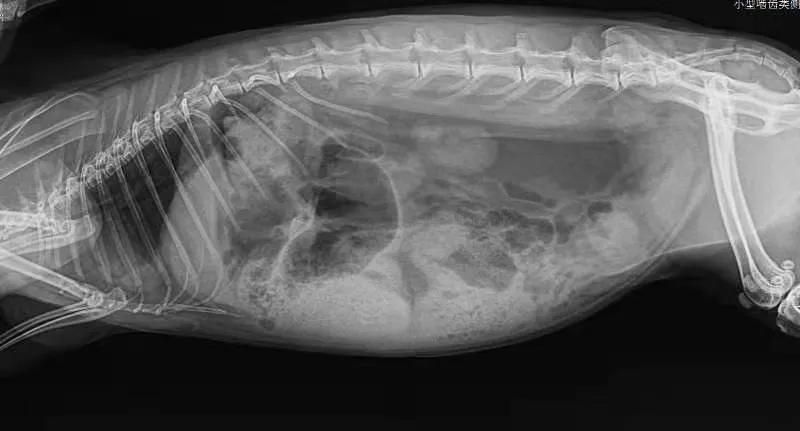

没有犹豫,立刻带它到当地动物诊所拍片,

医生看出来是胀气

表示对治疗兔子并不在行,教我怎么按摩它的肚子。我就坐在诊所帮“汤圆”按摩腹部,那是第一次“汤圆”在我身上趴那么久,它平时太凶悍了,连抓都很难抓到,从来没有一次在我怀里安稳呆过5秒钟。半小时后我要求再次拍片,显示气体有所移动。